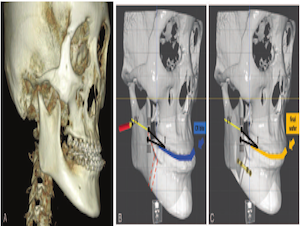

Contour Restoration of Over- Resected Mandibular Angle and Lower Border by Reduction Mandibuloplasty Using Three- Dimensional Planning and Computer-Aided Design and Manufacturing Custom-Made Titanium Implants

2jaw,BSSRO,CAD/CAM,contour restoration,customized,Digital orthognathics,Division of oral and Maxillofacial surgery,face-plate,FACEGIDE,lefort1,mandible augmentation,Mandibular,orthognathic surgery,osteotomy,over-resection,Prof. Jin Young Choi,Publication,R2GATE,restoration of contour,saw-guide,titanium implant,virtual surgery,wafer